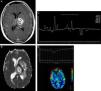

Distinguishing between PCNSL and infectious brain lesions is difficult but clinically relevant, particularly in immunocompromised patients. In this setting, nonconventional MRI may be used to differentiate focal brain lesions in PCNSL from neurotoxoplasmosis, cryptococcosis, tuberculosis and intracranial abscesses.21 DWI with ADC maps is useful to distinguish between toxoplasmosis and PCNSL. Early toxoplasmosis may be associated with areas of restricted diffusion on DWI; however, toxoplasmosis lesions have significantly greater diffusion than in PCNSL. ADC ratios that ranged from 1.0 to 1.6 have been reported for both PCNSL and toxoplasmosis, whereas ADC ratios greater than 1.6 were associated solely with toxoplasmosis.13 In addition, toxoplasmosis may be indicated by the presence of Lip and Lac and a decrease in the NAA/Cr ratio on MRS. Conversely, markedly elevated Cho levels would favor a PCNSL diagnosis.4,11 The accuracy of MRS is inversely proportional to the extension of necrosis (Figure 3).

A focal brain lesion in an AIDS patient (toxoplasmosis versus lymphoma). An axial T1 image after intravenous gadolinium administration (A) shows a large periventricular lesion in the left thalamus with extensive necrosis (asterisk) and thick peripheral enhancement. An axial apparent diffusion coefficient map (B) confirmed a very low signal intensity in the solid portion of the lesion (arrowheads) compared with the central area of necrosis (asterisk). Additionally, note the hyperintensity of the perilesional vasogenic edema. Proton magnetic resonance spectroscopy (C) confirmed the presence of elevated lipid and lactate (0.9–1.3ppm) and choline levels with reduced N-acetylaspartate levels. A magnetic resonance perfusion sequence (dynamic susceptibility contrast magnetic resonance image T2*) (D) confirmed the absence of neoangiogenesis (low relative cerebral blood volume). These features supported the diagnosis of lymphoma.